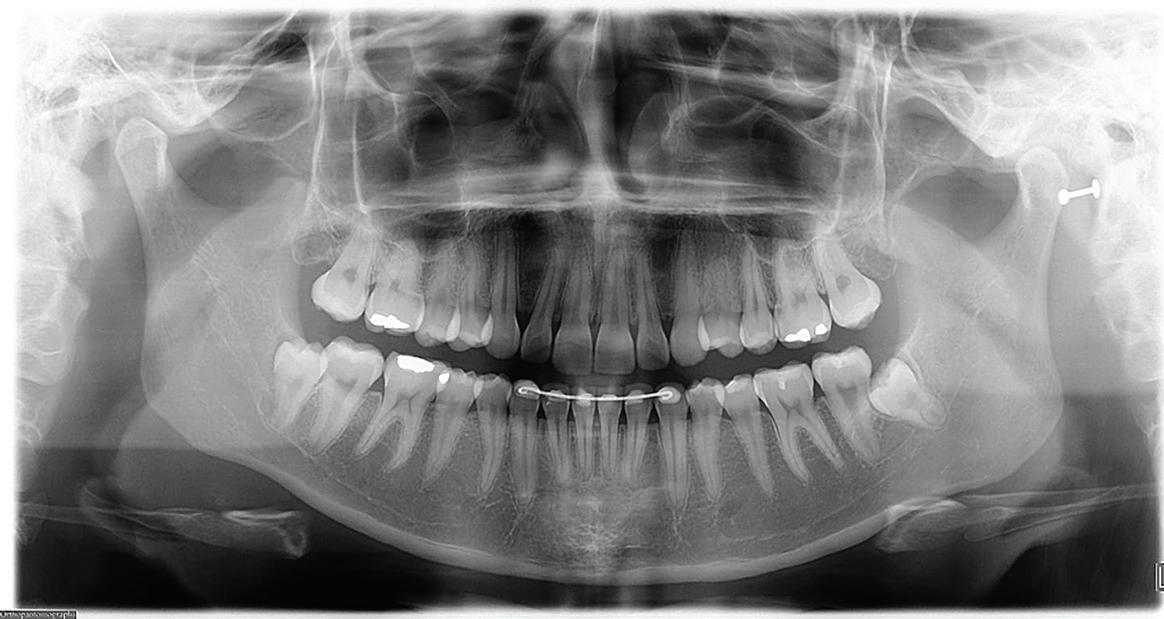

Root migration after coronectomy of impacted mandibular third molars: case reports

Gustavo Henrique de Souza Silva Enzo Balestrero

Jéssica Lemos Gulinelli

Pâmela Leticia dos Santos